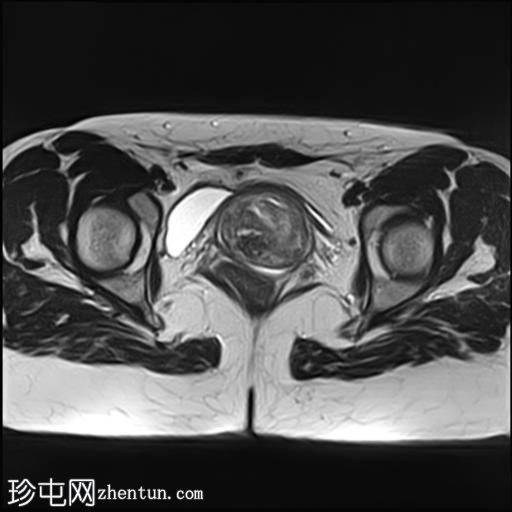

轴位

T2加权像

子宫增大,前倾后屈,可见多发大小不一、位置各异的壁内肌瘤(主要位于Figo 2、5和6区)。

一个边界清晰的带蒂宫腔内肿块经扩张的宫颈管脱出。T1加权像上呈等信号,T2加权像上呈中低信号,周围环绕着高信号的子宫内膜,静脉注射对比剂后呈明显不均匀强化。

双侧卵巢外观正常,可见小卵泡。